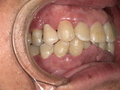

症例結果|Before / After

Before

- 詰め物が脱離

- 清潔感に欠ける状態

After

- 自然な白さ

- 違和感ゼロ

- 美しく機能的

👉 見た目も機能も大きく改善

治療詳細

- 年齢:50代男性

- 期間:約2週間(2回)

- 費用:セラミックジルコニア冠198,000円(税込)

土台 44,000円(税込)